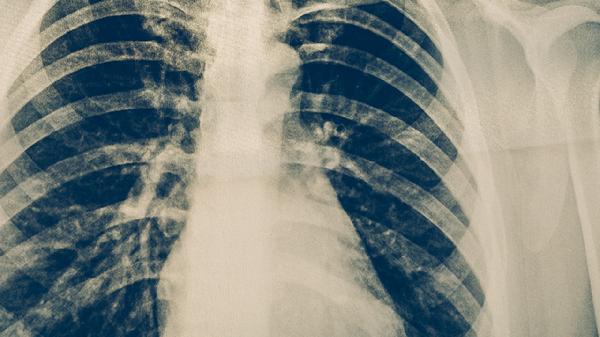

肺癌病人应该怎样保健

肺癌病人可通过调整饮食、适度运动、心理疏导、定期复查、避免危险因素等方式进行保健。肺癌可能与吸烟、空气污染、职业暴露、遗传等因素有关,通常表现为咳嗽、胸痛、咯血等症状。